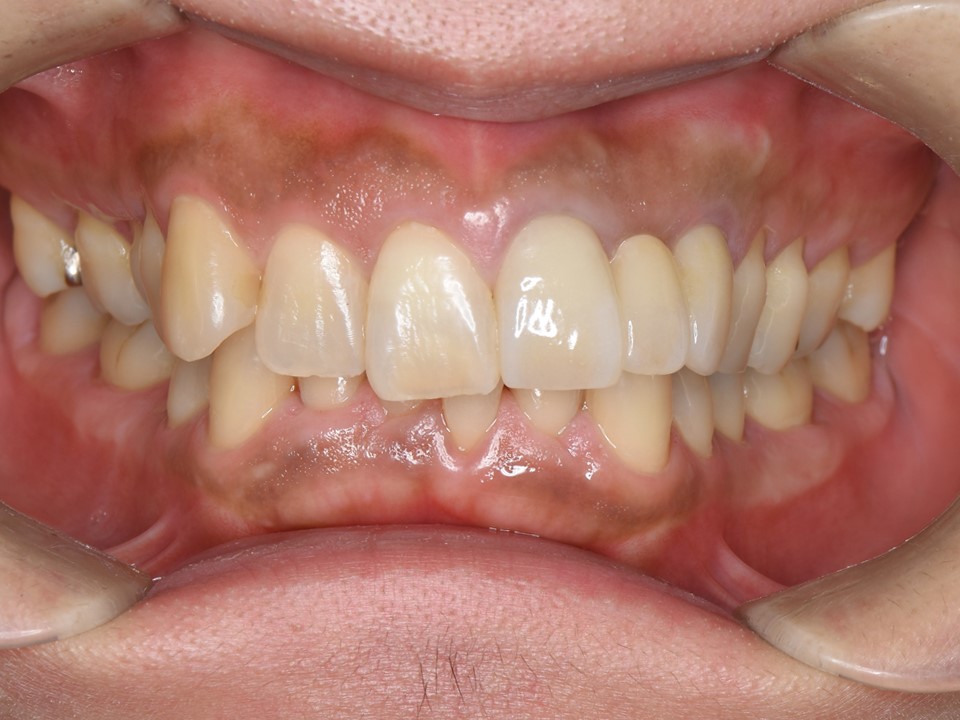

初診時。左側中切歯(矢印:向かって右)の変色を主訴に来院。外傷により歯冠の1/3が破折しており、コンポジットレジンにて修復がしてある。歯とコンポジットレジンの変色により、審美的な問題を起こしている。歯髄壊死が疑われた。

治療後。左側中切歯をオールセラミッククラウンにて補綴(ほてつ)を行った。主訴である審美障害は改善され、白く輝く美し口元になった。